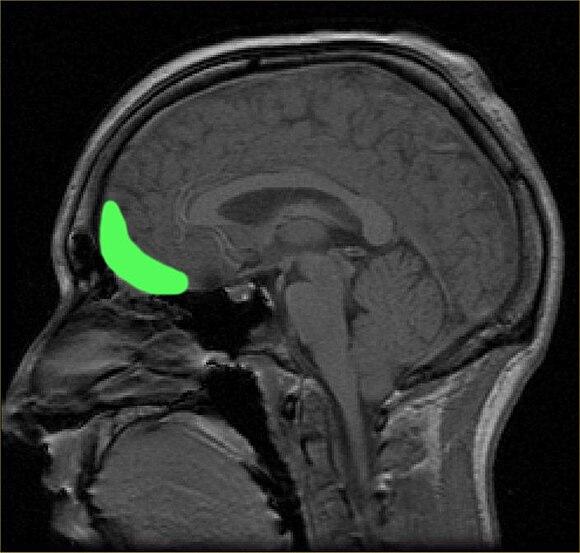

В исследовании приняли участие 352 взрослых футболиста-любителя. Ученые установили, что у тех, кто выполнял более 1000 ударов головой в год, наблюдались изменения в корковом интерфейсе серого и белого вещества (GWI) в орбитофронтальной области мозга, расположенной непосредственно за глазами.

Аспирантка Джоан Сонг, разработавшая метод анализа МРТ-изображений, отмечает, что у здоровых людей переход между тканями серого и белого вещества обычно резкий, тогда как у футболистов с большим количеством ударов головой этот переход становится менее четким.